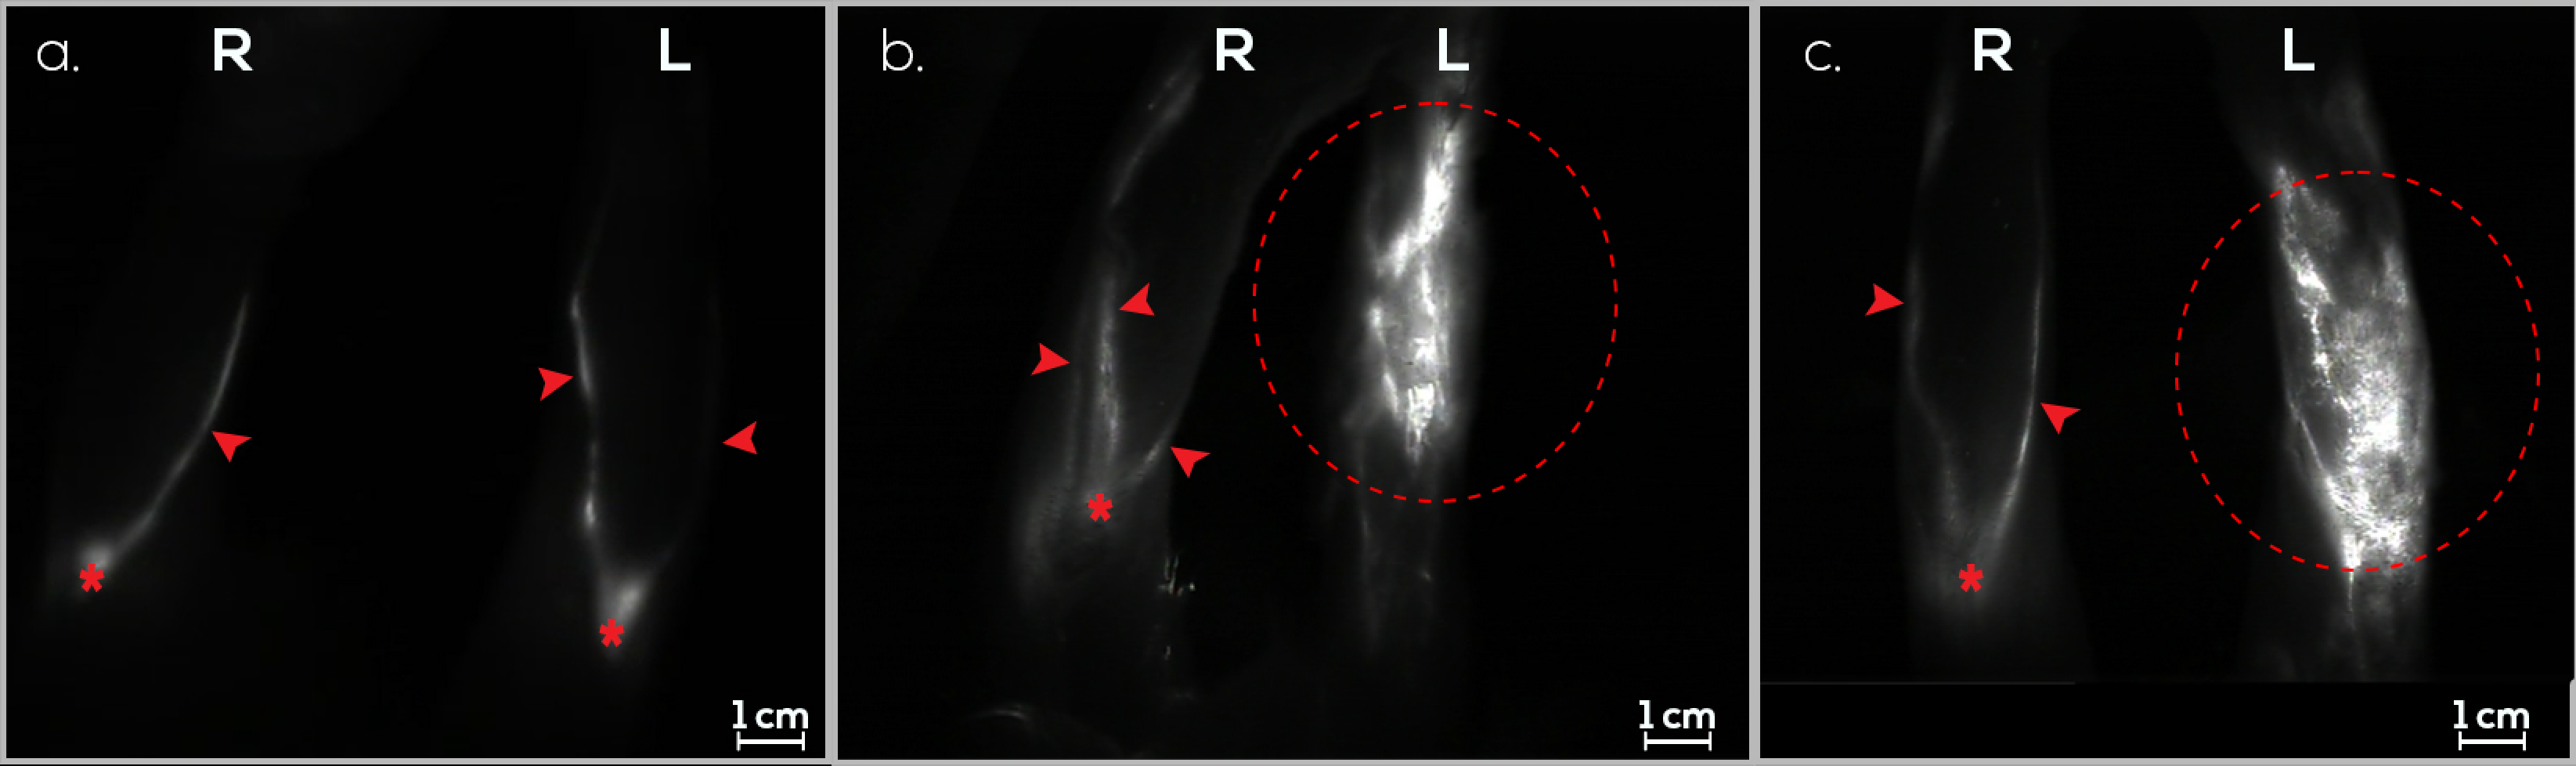

3.1. Treatment Group (G1)

3.3. Control Group (G3)

3.4. Follow-Up Assessments